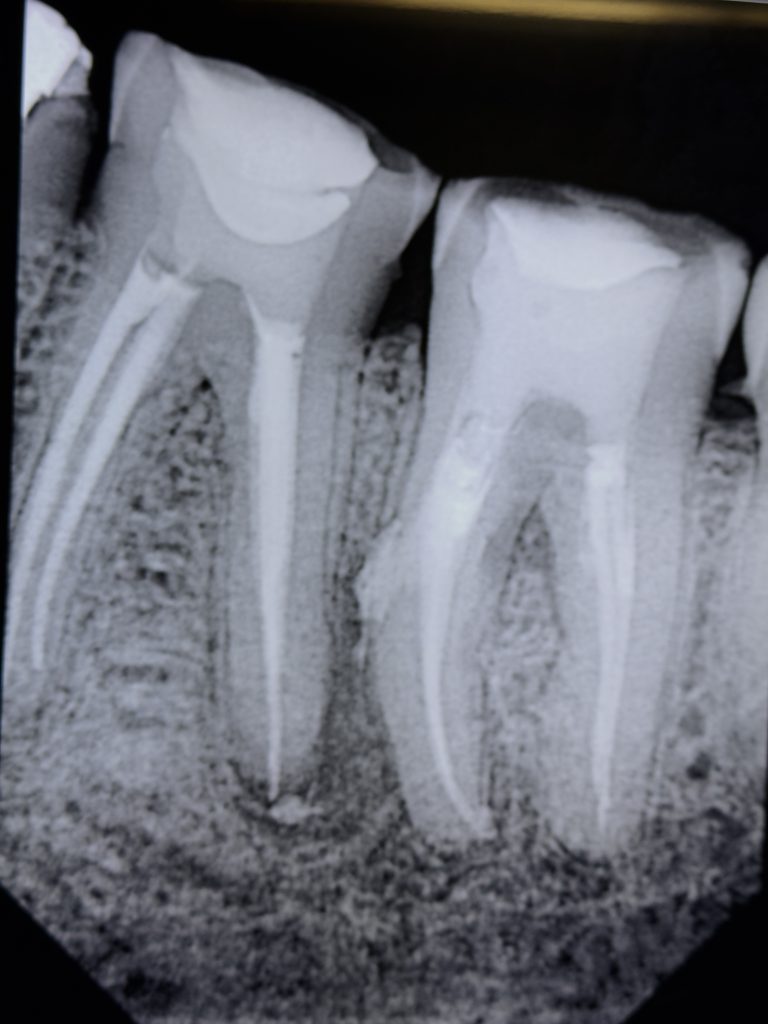

8️⃣ Post-Operative Evaluation

Radiograph confirmed dense obturation, sealed apices, and accurate restoration margins (Fig 9). At 1-month follow-up, both molars remained asymptomatic with proper occlusal function and no periapical tenderness.